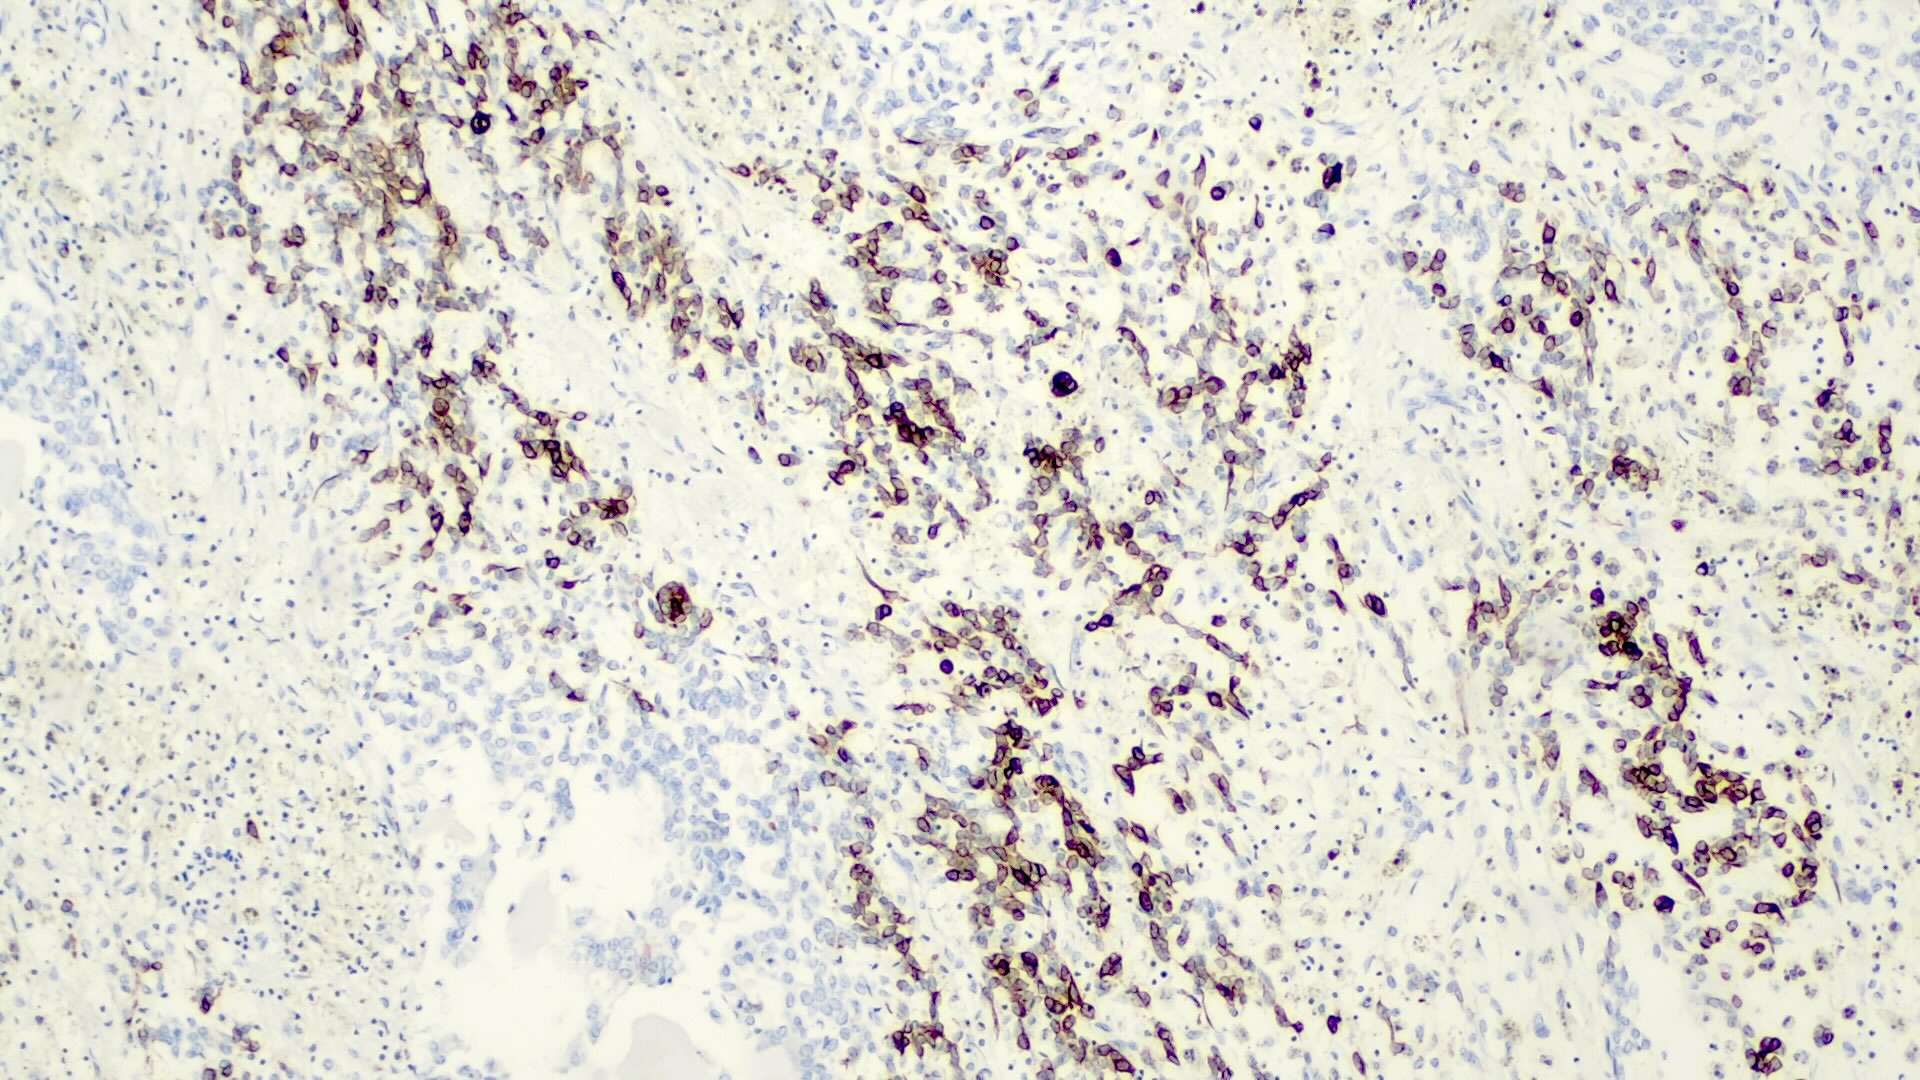

Negative stains

Negative stains

- INI1 / SMARCB1 is lost in a subset of small cell undifferentiated pattern, which has worse prognosis; some authors believe that this represents a malignant rhabdoid tumor rather than hepatoblastoma (Genes Chromosomes Cancer 2016;55:925)

Positive stains

- Alpha fetoprotein (negative in small cell type), chromogranin (fetal, epithelial subtypes, usually focal), CK8 / 18 (fetal, epithelial subtypes), CK19 (embryonal subtypes)

- Also EMA, HepPar1 (negative in small cell type), polyclonal CEA (canalicular pattern), vimentin

- Variable hCG, occasional HMB45 and melanin

- Beta catenin (nuclear) in small cell and embryonal types, delta-like protein (DLK), glypican 3 (negative in small cell type), glutamine synthetase